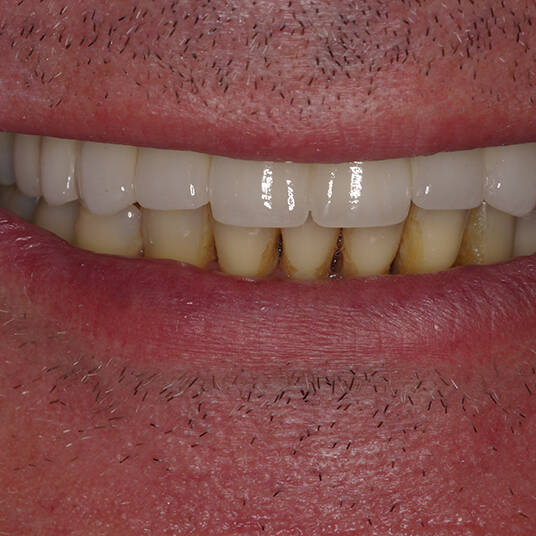

Na Clínica Pontes Odontologia, somos referência em implantes dentários em Fortaleza, oferecendo tratamentos de alta qualidade e tecnologia de ponta. Os implantes dentários são estruturas de titânio posicionadas cirurgicamente no osso maxilar ou mandibular para substituir as raízes dos dentes ausentes. Essa técnica permite a fixação de próteses personalizadas, restaurando a função mastigatória, a estética e a autoestima dos nossos pacientes.

Utilizamos a tecnologia CAD CAM, um sistema avançado que possibilita a confecção precisa das próteses dentárias diretamente sobre os implantes. Esse método inovador garante um ajuste perfeito, um resultado estético superior e proporciona muito mais conforto e durabilidade. Com o CAD CAM, nossos pacientes contam com um processo mais rápido e previsível para alcançar o sorriso desejado.